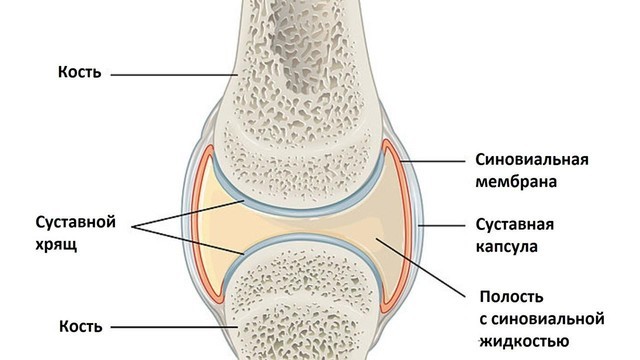

Остеоартрозом называют группу заболеваний суставного хряща и околосуставных тканей (рис. 1), в которых происходят дегенеративные нарушения. В основе остеоартроза лежит поражение гиалинового хряща, подлежащей (субхондральной) кости, синовиальной оболочки и капсулы сустава, околосуставных связок и мышц.

При остеоартрозе снижается плотность и эластичность хряща, происходит его истончение, разволокнение, растрескивание с образованием эрозий. Суставная поверхность прилежащей кости уплотняется и утолщается, суставная щель между хрящами сужается, формируются костные разрастания – остеофиты, похожие на шипы (рис. 2).

Они травмируют капсулу сустава, вызывая воспаление ее внутренней синовиальной оболочки (синовит). В результате возникает боль в суставе, он увеличивается и деформируется, а главное – не может полноценно работать.

Для улучшения выработки синовиальной жидкости, улучшения состояния хрящевой и костной ткани в полость сустава вводят гиалуроновую кислоту и собственную плазму, обогащенную тромбоцитами (РRР-терапия).

Эффект гиалуроновой кислоты объясняется повышением вязкости синовиальной жидкости, питания хряща, удержанием влаги в нем, стимуляцией синтеза коллагена. Нежелательные последствия применения гиалуроновой кислоты – аллергические реакции, инфекционные осложнения, короткий период действия.